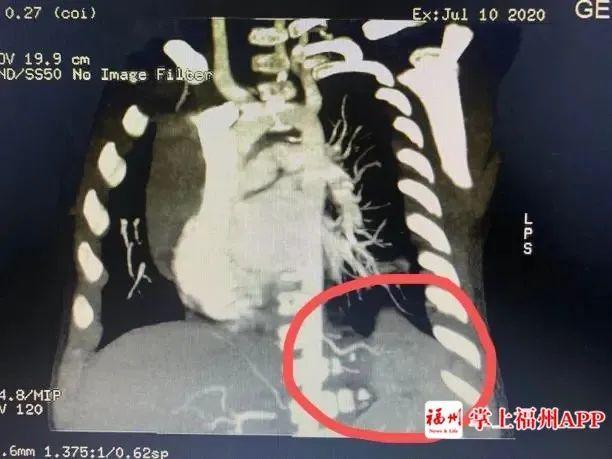

一个咳嗽这么难治愈吗?经过福建省福州儿童医院肺部CT检查,真相是小明的身体里“多了个肺”!!

医学上称为“肺隔离症”。

肺隔离症是一种先天性肺畸形,临床少见,其发病率约占先天性肺畸形的0.15% ~6.45%,一般无明显临床症状,多在合并肺内感染时与正常肺组织相通出现咳嗽、咳痰、咯血等症状,且反复发作,临床易误诊。

●增强CT结合三维血管重建发现异常供血可以确诊